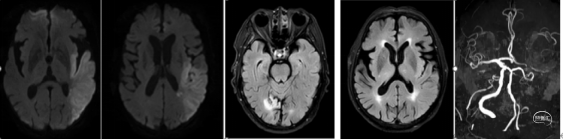

术前讨论:患者左侧颈总动脉闭塞,脑梗死诊断明确,发病12小时,NIHSS 15分,DWI-ASPECT 6分, DWI-Flair错配,静脉溶栓效果欠佳,急诊介入开通指征明确。

通路建立:8F短鞘,交换8F长鞘、5F多功能导管行脑血管。造影示:左侧颈总动脉闭塞,右侧颈内动脉-前交通动脉向左侧大脑中动脉部分代偿供血;左侧大脑中动脉下干闭塞。

抽吸后造影示:左侧颈总动脉复通,未见明显血栓逃逸;左侧大脑中动脉下干闭塞同术前。

微导管超选至下干近心端推注5ml替罗非班,后造影示下干部分再通,颈内动脉造影示左侧颈内动脉-大脑中动脉复通,eTICI 3级。

术后情况:术后第二天复查CTA提示:未见明显出血,左侧颈总动脉-大脑中动脉通畅。患者术后5天转科至康复科,术后1月NIHSS 5分,可独立行走.

CT示未见明显出血,头颅MRI示脑桥偏左DWI高信号,考虑急性脑梗死,头MRA示基底动脉闭塞。

患者及家属商议后拒绝手术,后症状进展加重,复查影像再次评估,同意手术。查体:嗜睡,重度构音障碍,右侧中枢性面舌瘫,右肢肌力0级,右侧巴氏征(+)。NIHSS 15分。

术后24h CT:脑桥低密度,复查CTA:基底动脉局部中度狭窄。

术后36h查体:神清,构音障碍,双瞳孔等大,等圆,右上肢肌力1级,右下肢肌力III-级,左肢肌力V级,肌张力可,腱反射(++),右侧巴氏征(+)NIHSS 8分。